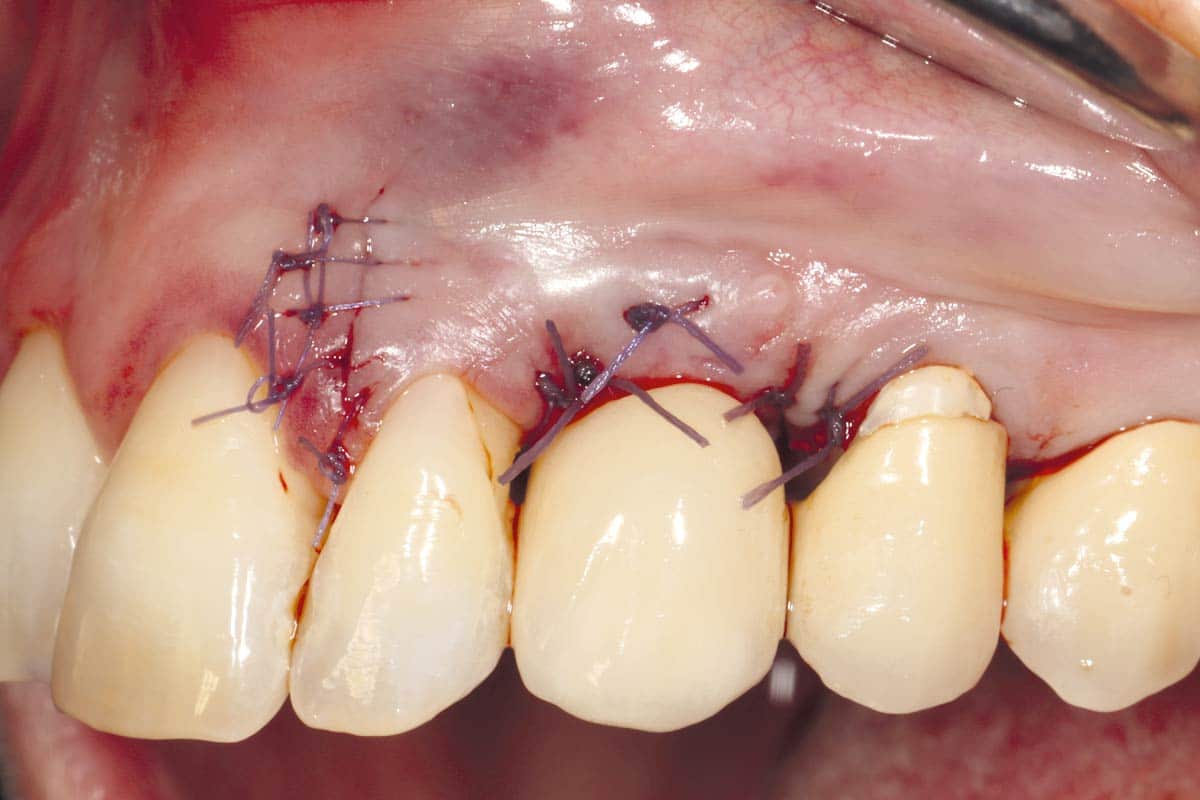

A patient presented with a peri-implant bone defect characterized by bone resorption compromising the stability and long-term prognosis of the implant. To re-establish sufficient bone volume and ensure implant longevity, a regenerative surgical intervention was performed using a guided bone regeneration (GBR) approach. The treatment featured cerabone® plus for grafting, complemented by the Shield Technique using fully resorbable magnesium-based NOVAMag® SHIELD to guide bone regeneration.